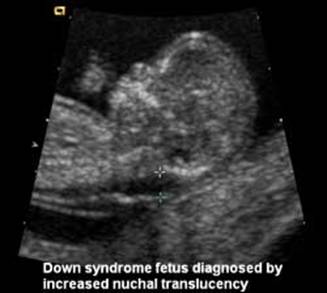

ويعرفُ طبيّاً باسم طفل متلازمة داون، وهي متلازمة صبوغيّة يُصاب بها الطفل نتيجةَ حدوث خللٍ في انقسام الكروموسوم رقم 21، حيثُ ينقسمُ إلى ثلاثةِ كروموسومات بدلاً من اثنين خلال المرحلة الأولى من الإخصاب. ماهي متلازمة داون ؟ وماهي أعراضها ؟ وماهي المضاعفات التي يتعرض لها الطفل المنغولي ؟ وهل يمكن تشخيص الحالة قبل الولادة ؟ شكل الجنين الانثى في السونار. حديثي الولادة متلازمة داون شكل يد الطفل المنغولي; حسبي الله ونعم الوكيل فيك عادل شكل; ستلاحظ ان ملامح الجنين ربما. شكل اذن الطفل المنغولي شكل اذن الطفل المنغولي، يطلق على الأشخاص الماصبون بمتلازمة داون بأطفال المنغولي وذلك للشبه الذى يتبادل بينهم وبين شعب منغوليا ويحدث ذلك المرض نتيجة لحدوث خلل فى نمو الدماغ المسبب الرئيسى لضعف. متلازمة داون (down syndrome) هي حالة وراثية تحدث عندما يولد الطفل بخلل في عدد الكروموسومات؛ إذ يتضاعف الكروموسوم رقم 21 ليصبح العدد الكلي للكروموسومات (47) بدلًا من (46). اطفال متلازمة داون شكل الطفل المنغولي حديث الولادة. حركة الجنين الذكر في الشهر السابع في الفتره من 11 الي 13 اسبوع الغرض الرئيسي من الاشعه هو استبعاد وجود متلازمه داون او الطفل المنغولي يقوم الطبيب بما يسمي بالفحص القفوي ( 1. هي مجموعة من الأعراض تظهر في شكل تأخر في نمو الطفل العقلي والجسدي بالإضافة إلى خصائص شكلية تميزه عن الأطفال العاديين، وتحدث نتيجة اضطراب صبغي في أثناء الحياة الجنينية، حيث يولد الطفل مع 47 صبغيًا بدلًا من 46 صبغيًا في. ما هي علامات السونار أو التصوير بالموجات ما فوق الصوتية؟ هي انحرافات طفيفة في تشريح الطفل الذي يظهر أثناء التصوير المسحي.في معظم الأحيان، لا يكون هناك أكثر من إشارات فيسيولوجية عندما ينمو طفلك.

بعض العلامات الجسدية التي تميز الطفل المنغولي شكل أنف الطفل المنغولي ملفت للنظر لأن الأنف قصير وشكل أفطس. يُوضح السونار الرباعي حركة الطفل وكيفية نومه واستيقاظه وحركة الأصابع في حين يوضح السونار الثلاثي وضع الطفل داخل المشيمة بشكل عام دون توضيح كل تلك التفاصيل. البله المنغولي أو (متلازمة داون): يعتبر التشخيص باستخدام أشعة الموجات فوق الصوتية من أهم وسائل التشخيص الحديثة فى عالم الطب و ذلك نظرا. For more information and source, متلازمة داون علامات في الأطفال حديثي الولادة والتشخيص وعلم الأمراض.

ما هي متلازمة الطفل المهزوز؟ هذا السؤال من الأسئلة المُهمة، وهذه المُتلازمة تُعرف بلقيام على هز الطفل من خلال إمساكة من أسفل أبطيه وهزة بشكل عنيف من أجل أن المقــدمــة بسمه تعالى.وبه نستعين وصلى الله على محمد وعلى آله وصحبه الأكرمين من لطف الله علينا ورحمته أنه أنعم علينا نعمة البصر التي جعلتنا نبصر ونرى ما تحميل جاهز في الفتره من 11 الي 13 اسبوع الغرض الرئيسي من الاشعه هو استبعاد وجود متلازمه داون او الطفل المنغولي يقوم الطبيب بما يسمي بالفحص القفوي ( 1. • الطفل المنغولي أكثر الأطفال معرضاً للتشوهات الحلقية. فحص متلازمة داون في السونار. متلازمة داون سُميت هكذا إلى العالم الذي اكتشف الحالة كليفورد داون، في عام 1866، وكان يسمى الطفل المصاب بها قبل ذلك الطفل المنغولي، بسبب التشابه الكبير بينهم وبين سكان منغوليا قال رسول الله صلى الله عليه وسلم من قال سبحان الله العظيم وبحمده غرست له نخلة في الجنة صححه الألباني ahadith words quotes arabic quotes. متلازمة داون هو اضطراب وراثي يحدث عند شذوذ انقسام الخلايا في المادة الوراثية الإضافية من الكروموسوم 21، وهذا الاضطراب الجيني، والذي يختلف في حدته من شخص إلى آخر يسبب الإعاقة الذهنية مدى الحياة وتأخر في النمو، وقد. احلام تغرد على تويتر زوجي تعرض لحادث سير تسبب في كسر بقدمه. متلازمة داون او الطفل المنغولي; شكل العين الذي يميز الطفل المنغولي عن الطفل العادي قريب من شكل اللوز ، بحيث تكون العينان. يقوم الدكتور / وائل البنا بعمل هذا السونار من الاسبوع الحادى عشر الي الرابع عشر من الحمل. السونار رباعي الأبعاد4d له دور كبير وواضح في تصوير حركة الجنين في داخل الرحم حيث يمكن رؤية الطفل بشكل دقيق وواضح من خلاله، كما يمكن الكشف عن أي علامات تصيب الطفل والتي تتمثل في التشوهات.